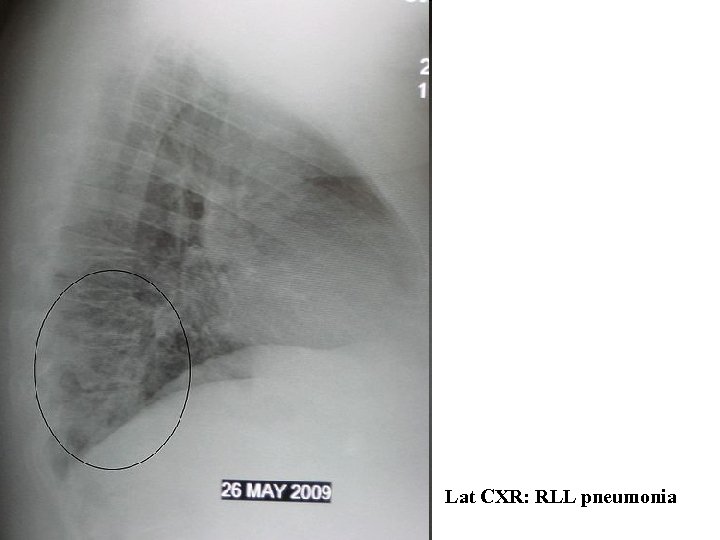

Lat CXR: RLL pneumonia